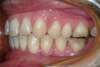

Cas1 - Début de traitement